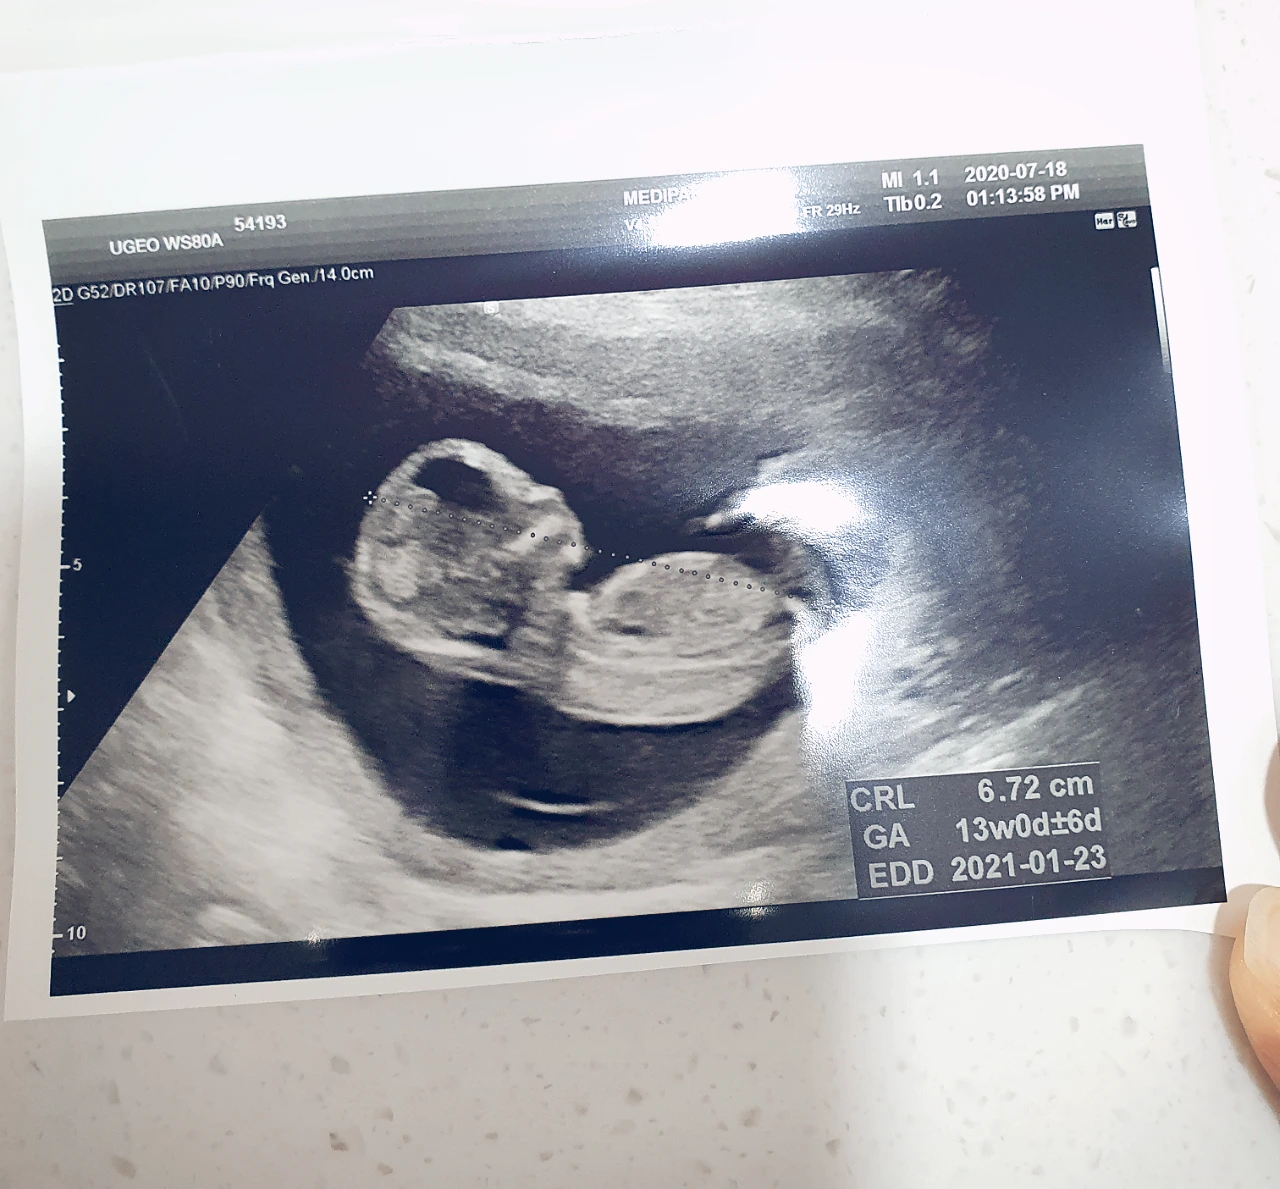

9주차(좌)에서 13주차(우)로 폭풍 성장한 셋째의 초음파 사진